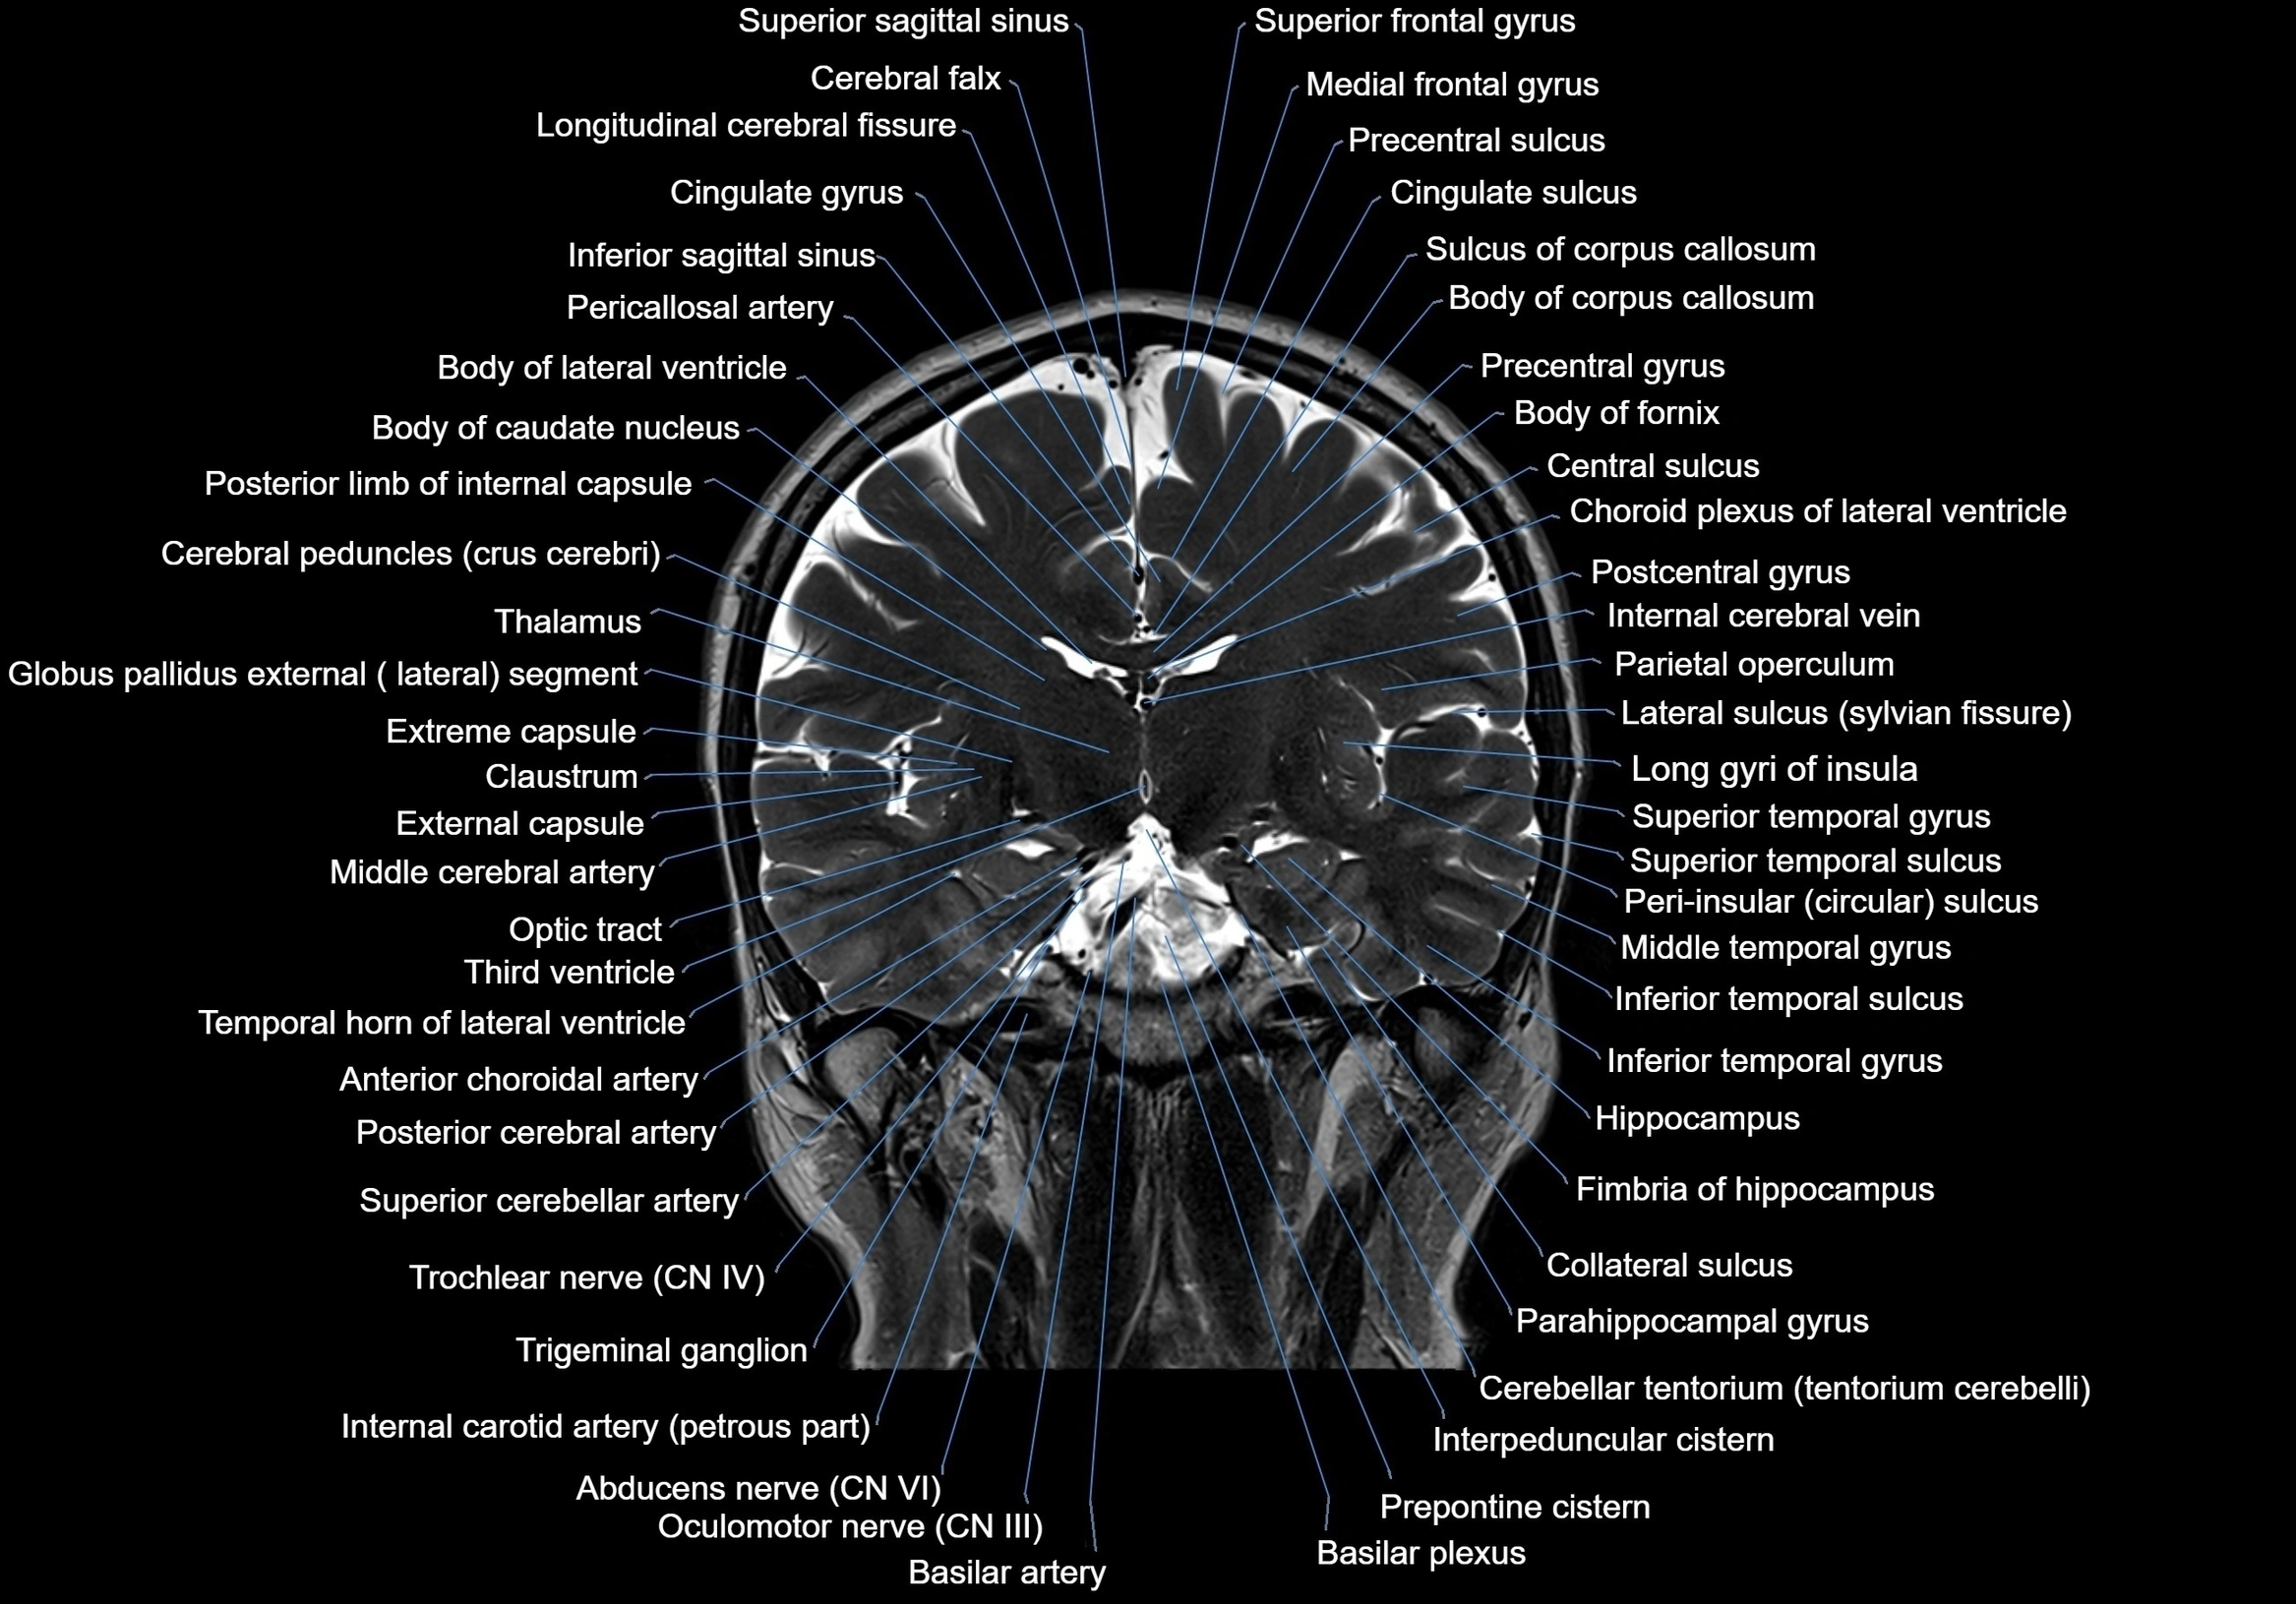

MRI images